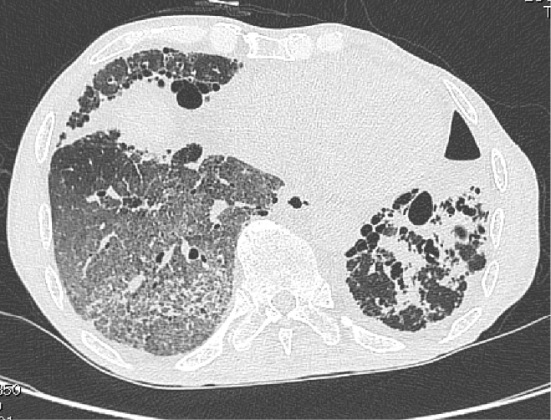

・肺胞出血:

IgA血管炎で肺胞出血をきたしたケースとリテラチャーレビュー